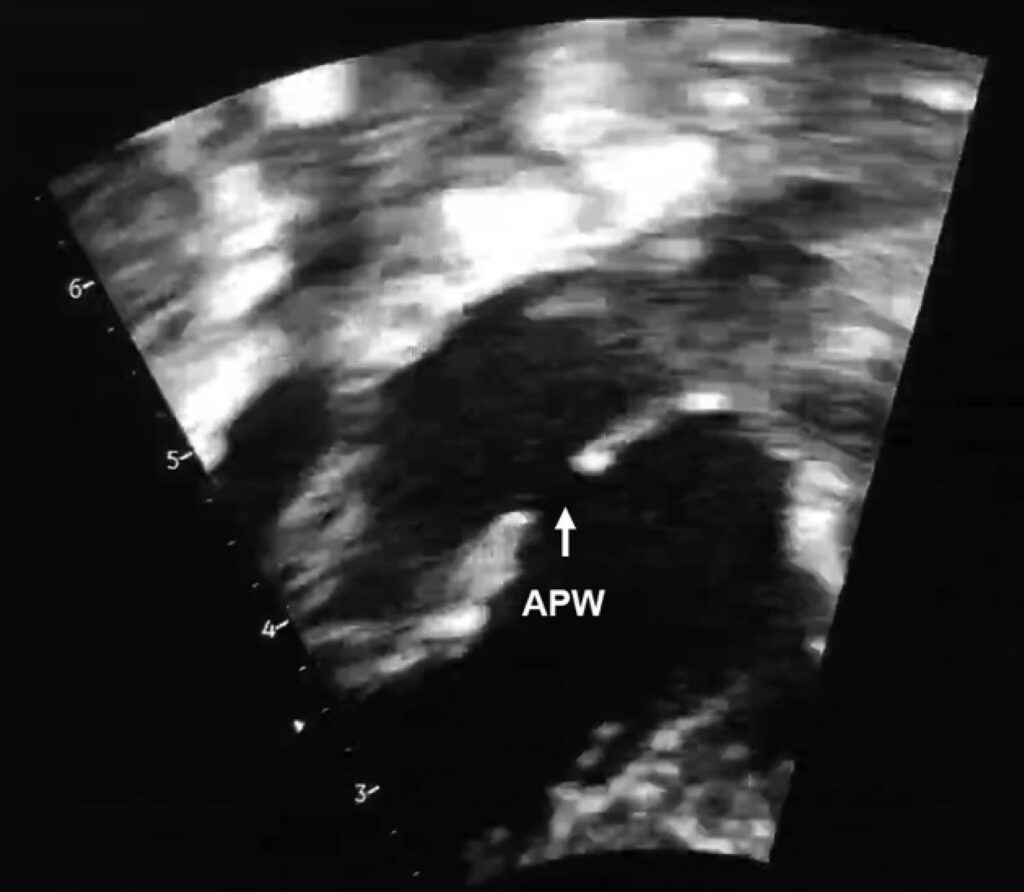

Figura 1

– O ecocardiograma mostrou uma grande JAP de 5,0 mm. JAP: Janela Aortopulmonar.